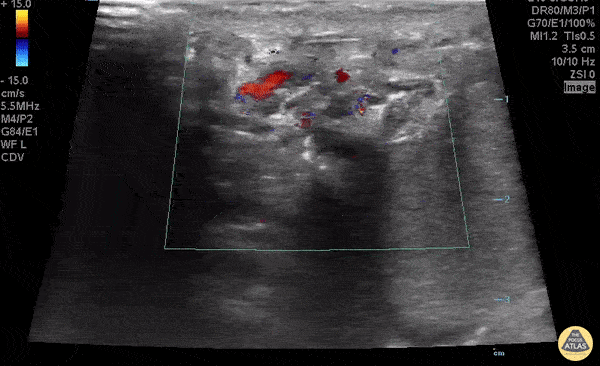

Peds-Genitourinary - Whirlpool Sign

16 yo male who presents with left testicular pain. Exam with horizontal left testicle. POCUS shows blood flow to both testicles, however left distal spermatic cord demonstrates whirlpool sign, consistent with intermittent/partial torsion. Dr. Paul Khalil and Dr. Joshua Kim - University of Louisville @kjosh317